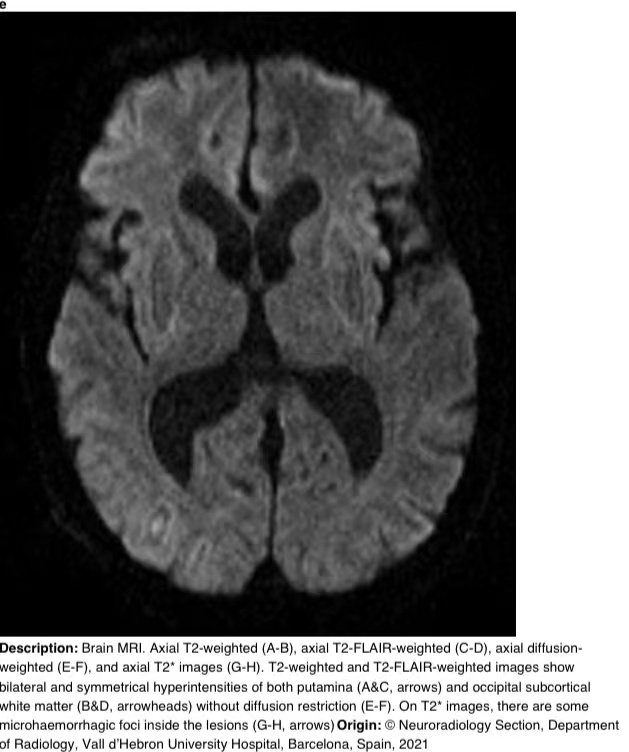

在16天的随访中,脑部MRI显示壳核和枕下皮质下白质上对称的T2/FLAIR高信号。T2图像显示病变内有微出血(图3)。

图3 a-h 脑部核磁共振成像。轴向T2加权(A-B)、轴向T2 FLAIR加权(C-D)、轴向弥散加权(E-F)和轴向T2图像(G-H)。T2加权和T2 FLAIR加权图像显示双侧和对称的壳核高信号(A和C,箭头)和枕下皮质下白质高信号(B和D,箭头),无弥散限制(E-F)。在T2图像上,病变内有一些微出血病灶(G-H,箭头)。